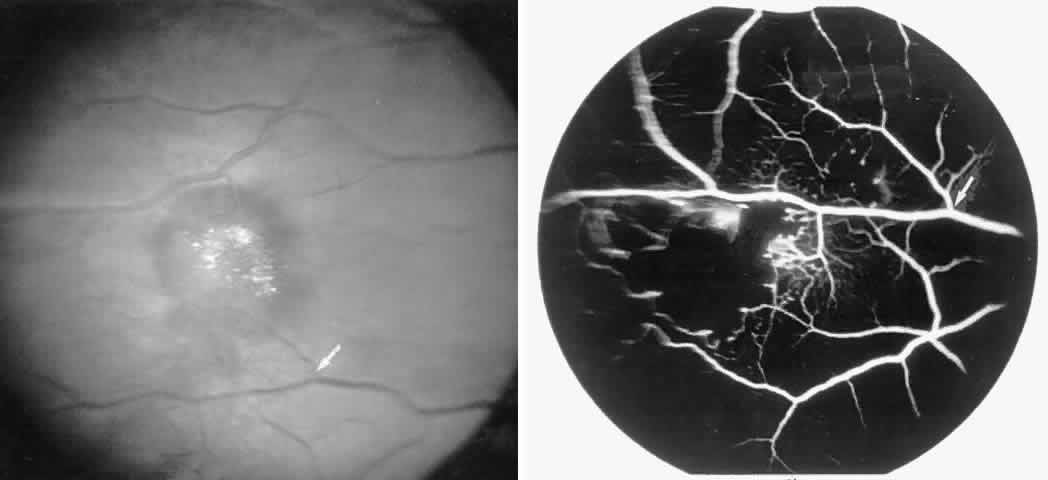

Retinal Hemorrhages, Iridescent Spots, and Black Sunbursts

Retinal hemorrhages (“salmon patches”), found most commonly in the equatorial periphery, can be observed after an abrupt occlusion and rupture of an intermediate-sized retinal arteriole (Fig. 16).113 Because the hemorrhages typically appear adjacent or distal to an intraluminal obstruction, it is likely that ischemic necrosis causes a weakening of the vessel wall and that reperfusion of the vessel causes a rupture of the damaged vessel wall, resulting in a hemorrhage (Fig. 17).100 Acutely, these hemorrhages are bright red, but after several days, the partially degenerated blood acquires a characteristic orange-red color (hence the name salmon patch). In most cases, these hemorrhages are asymptomatic. The majority of these hemorrhages remain confined to the sensory retina; however, blood may leak through the internal limiting membrane into the vitreous or dissect deeper into the subretinal space (Fig. 18).114 Resolution occurs over days to weeks and may result in a focal area of atrophic split retina (a “schisis” cavity), a pigmented retinal scar, or a grayish-white vitreous deposit, depending on the location of the hemorrhage (Color Plate 1B through G).115 The blood is slowly cleared by macrophages.

Fig. 16. A 15-year-old boy with homozygous sickle cell anemia, stage II sickle cell retinopathy, and an ISC count of 23.8% noted an acute nasal visual field defect in the right eye. Visual acuity was 20/20 OU. A. Photograph of the right eye demonstrating arteriolar occlusions in the temporal macula, with white, edematous retina and cherry red spot in the fovea. Note the arteriolar occlusion inferiorly, with darkening of the vessel distal to the occlusion site (black arrow). (The closed white arrow identifies a corresponding arteriolar bifurcation in A through D.) B. Red-free photograph 6 days later showing two salmon-patch hemorrhages. The superior salmon-patch hemorrhage overlies the occlusion site noted in A. Note the distal movement of the occlusion site along the arteriole (black arrow). C. Early fluorescein angiogram, showing loss of capillary network in the temporal macula but preservation of the perifoveal network. D. Late phase of the fluorescein angiogram, showing salmon-patch hemorrhages temporally and the occlusions distal to the hemorrhages (open arrows).E. Visual field performed 9 months later shows persistent nasal field defect, but visual acuity has remained 20/20. F. Two years later, a fluorescein angiogram shows a cilioretinal artery perfusing the nasal macula. G. The late phase of the fluorescein angiogram demonstrates complete loss of the temporal macular capillary network.

Fig. 17. A 27-year-old man with homozygous sickle cell anemia. A. A small amount of fluorescein leakage is seen from an arteriole in the inferior nasal peripheral retina (arrow). B. Four months later, a salmon-patch hemorrhage is seen over the leakage site noted in A (arrow). Note the distal arteriolar occlusion, which probably caused increased intravascular pressure and vessel rupture at the area of leakage noted previously.